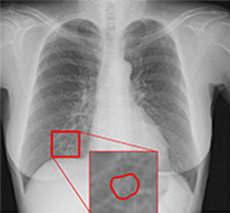

胸部経時差分処理

Temporal Subtraction処理

注意:赤枠は実際には表示されません。

Temporal Subtraction処理は、独自のアルゴリズム補正をもとに、胸部画像の現在と過去の差分画像を生成する画像処理技術です。

そこで、現在と過去の差分画像を生成し「変化の有無」を可視化することで、診断精度の向上と時間短縮が期待でき、胸部読影を強力にサポートします。

◆変化が可視化され、新規病変の認識がしやすくなる。

経時変化の差がドーナツ形状として現れることで、一見「変化なし」としがちな病変の大きさ変化が認識可能です。